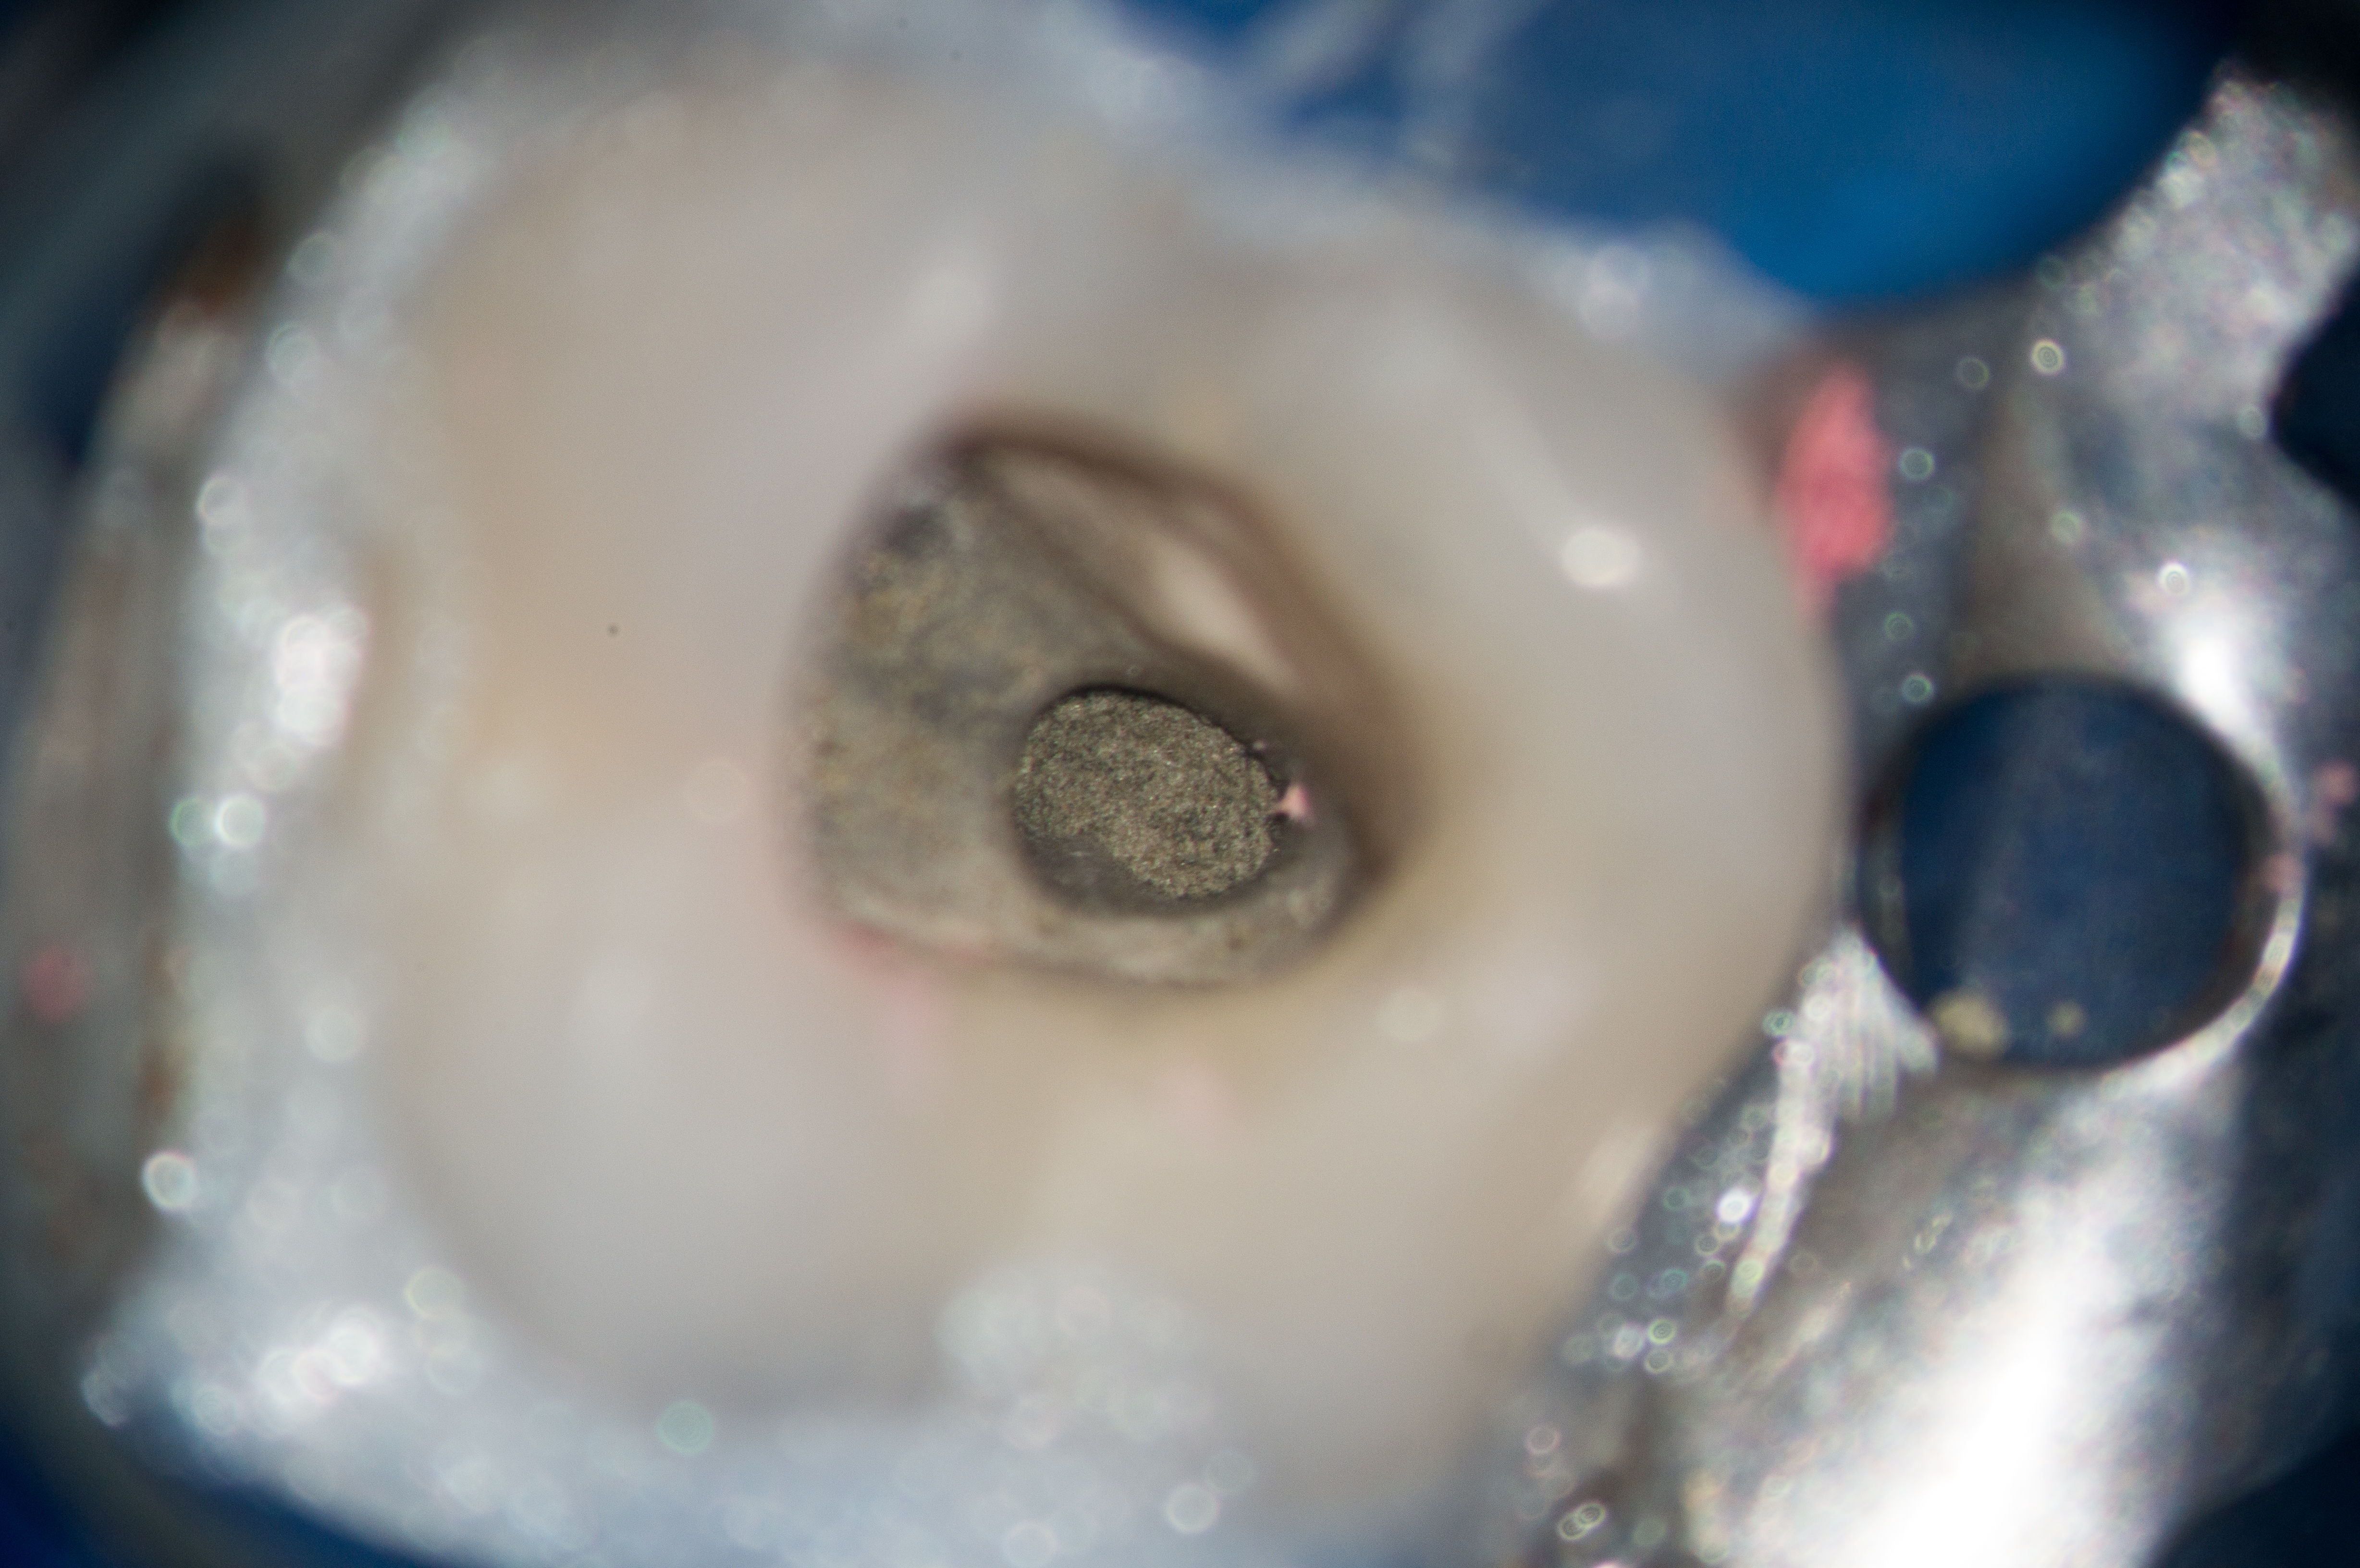

Kaps Fototubus für Sony NEX